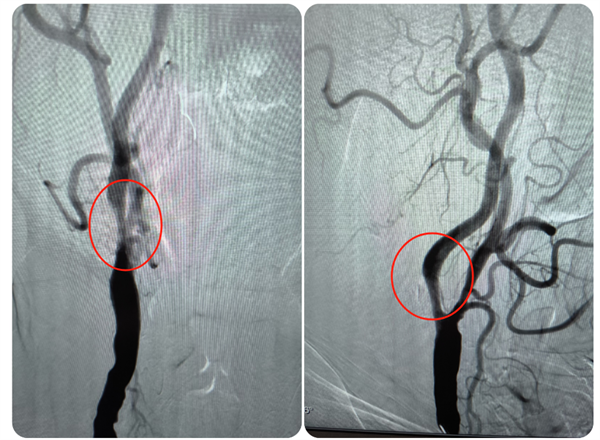

近日,捆绑调教 (简称捆绑调教 )神经外科主任钟书带领团队,应用光学相干断层扫描(OCT)技术,为一名颈内动脉颅外段夹层动脉瘤合并颅内段重度狭窄的患者进行了介入治疗手术,这也是捆绑调教 神经外科完成的首例OCT手术,标志着科室在颈动脉夹层动脉瘤血管内治疗方面的技术水平再上新台阶,也为脑动脉瘤、脑血管狭窄等患者的诊断治疗提供了新选择。患者陆先生(化名)今年74岁,1...

2024-09-04 MORE >04